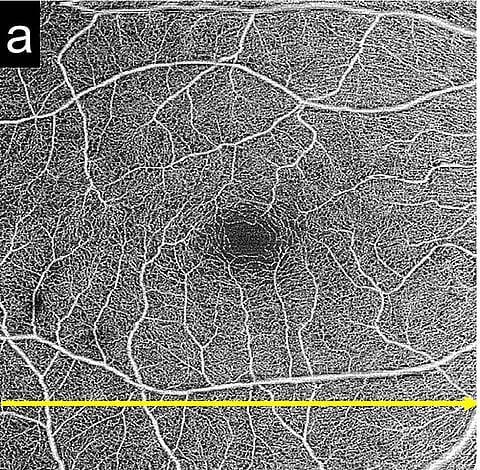

Pachyvessels are pathologically dilated large choroidal vessels and are associated with the pathogenesis of several pachychoroid-related disorders, including central serous chorioretinopathy. We aimed to investigate the prevalence of and risk factors for pachyvessels in the Japanese population. We included 316 participants (aged ≥ 40 years) with normal right eyes. The presence of pachyvessels (vertical diameter > 300 µm, distance to the retinal pigment epithelium < 50 µm) was determined using 6 × 6 mm macular swept-source optical coherence tomography images, and associated risk factors were investigated. Subfoveal choroidal thickness was measured, and its associated risk factors investigated. The overall prevalence of pachychoroids was 9.5%. Regression analysis showed that a younger age, shorter axial length, male sex, and smoking were significantly associated with the presence of pachyvessels (p = 0.047; odds ratio [OR] 0.96 per year, p = 0.021; OR 0.61 per 1 mm, p = 0.012; OR 3.08 vs. female, and p = 0.011; OR 3.15 vs. non-smoker, respectively) and greater choroidal thickness (p < 0.001, p < 0.001, p < 0.003, and p < 0.017, respectively). The results were consistent with other research findings which showed that pachychoroid-related disorders such as central serous chorioretinopathy were associated with younger age, male sex, shorter axial length, and smoking. Smoking may be associated with choroidal circulatory disturbance in the Japanese population.

Pachyvessels are large, inwardly displaced, pathologically dilated choroidal vessels. Pachyvessels can cause focal choriocapillaris thinning and are associated with the pathogenesis of central serous chorioretinopathy (CSC)1. In optical coherence tomography (OCT) angiography images of CSC eyes, the area of choriocapillaris flow void was found to be high2, and the location of the choriocapillaris flow void was associated with the distribution of the underlying choroidal vessels3,4. Studies suggest that pachyvessels impair choriocapillaris and may be responsible for retinal pigment epithelium (RPE) damage, resulting in CSC. Therefore, pachyvessels may be a preclinical sign of CSC, and normal eyes with pachyvessels may have a potential risk of CSC.

Baek et al. reported that the prevalence of pachyvessels was 25%, 46%, 85%, 96%, and 100% in non-neovascular age-related macular degeneration (AMD), neovascular AMD, thin choroid polypoidal choroidal vasculopathy (PCV), thick choroid PCV, and CSC eyes, respectively5. However, the prevalence of pachyvessels in the normal healthy population without degenerative disease has not been studied. Thus, investigation of pachyvessel prevalence will increase understanding of its pathogenesis in CSC, PCV, and AMD. Therefore, our study evaluated the prevalence of pachyvessels and associated risk factors in a normal Japanese population. In addition, the risk factors associated with increased subfoveal choroidal thickness were studied.